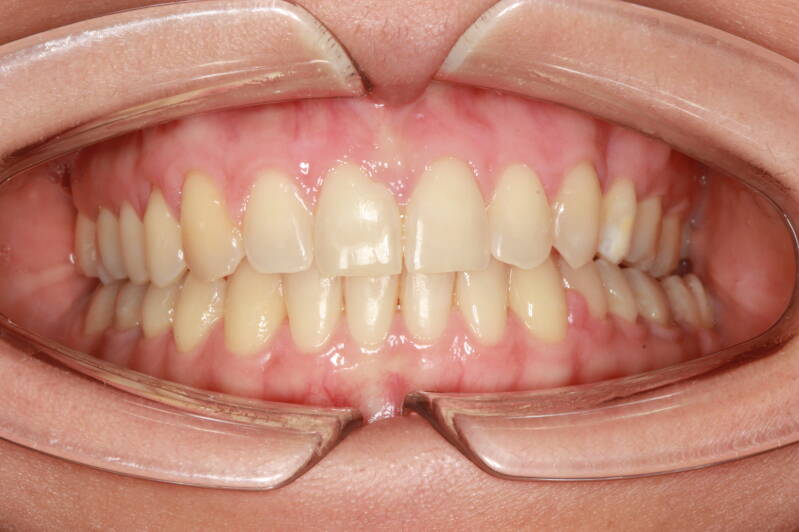

FOTO FINALI DOPO 24 MESI CIRCA DI TERAPA ORTODONTICA FISSA

Abbiamo appena portato a termine questo caso che presentava in arcata superiore il primo premolare di sinistra completamente fuori arcata sovrapposto al secondo premolare ed il canino ruotato.

in arcata inferiore invece abbiamo estratto il secondo molare di sinistra perso per carie deostruente e mesializzato il terzo molare in modo da chiudere lo spazio e non ricorrere all'inserimento di protesi implantare.